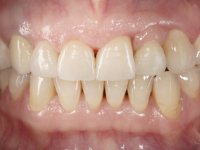

Paciente do sexo feminino, com 47 anos não fumadora. Apresentou-se na consulta com o dente 1.3 com tratamento endodôntico e com um espigão falso coto fundido, reabilitado com uma coroa provisória. Os dois incisivos laterais superiores são conoides e de reduzida dimensão. O dente 2.2 apresenta mobilidade, consentânea com uma significativa reabsorção óssea entre o dente 2.1 e o dente 2.3 Os dois incisivos centrais estão separados por um diastema de 3mm e o dente 2.3 apresenta uma oclusão cruzada com o dente antagonista. Verifica-se também a ausência de alguns dentes posteriores e uma higiene oral razoável. Na segunda intervenção realizada passados 8 anos, verificou-se que os incisivos centrais superiores se apresentavam cromaticamente mais escuros e apresentavam um sulco longitudinal no esmalte que estando pigmentado comprometia esteticamente o sorriso. O trabalho realizado na primeira fase do tratamento mostrava-se competente estética e funcionalmente. Por fim, um ano após a última intervenção, a paciente apresentou-se com uma fratura da faceta colocada no dente 2.1 provavelmente em resultado de estar em contacto com o coto do implante. A rigidez da anquilose implantar, pode ter sido a causa desta fratura. Outros casos deste tipo de fratura já foram observados por mim em situações clínicas idênticas. A faceta do dente 1.2 apresentava-se esteticamente comprometida e a própria estrutura dentária apresentava uma pequena cárie e, pelo que se recomendaria a sua substituição.

O tratamento iniciou-se com a re -preparação do coto do espigão falso coto fundido, com o objetivo de colocar as linhas de acabamento cervical com uma localização intra-sulcular e simultaneamente confecionar uma coroa provisória adaptada. Com um tratamento ortodôntico muito simples, fechou-se o diastema entre os incisivos centrais superiores e estabilizou-se esta posição com um arame colocado na superfície palatina dos centrais, funcionando como contenção. Posteriormente procurou-se fazer uma tração ortodôntica lenta do dente 2.2 com o intuito de diminuir, ainda que muito ligeiramente a perda óssea vertical nessa zona. Finalizada a tração, foi feita a extração do dente 2.2 e a zona foi reabilitada provisoriamente com uma coroa de resina composta colada aos dentes adjacentes. Foi colocado um implante dentário na zona do dente 2.2 sendo novamente colada a coroa provisória em resina, reabilitando provisoriamente a paciente durante o período de osseointegração. No dente 1.3 foi feita uma gengivectomia com bisturi elétrico, com a intenção de subir o nível cervical do 1.3 conseguindo uma maior harmonia com o dente 2.3. Estabilizados os tecidos moles, foi feita uma impressão com a técnica de moldeira aberta, utilizando silicones de adição de consistência “putty” e “light”. A recolha da cor, tanto da componente dentária como dos tecidos moles foi feita pelo ceramista no consultório.  No laboratório as impressões foram passadas a gesso e deram origem a modelos de trabalho que foram devidamente analisados. Foi decidido confecionar um “abutment” metalo-cerâmico aparafusado sobre o implante. Este “abutment” foi fundido com uma liga nobre e posteriormente revestido a cerâmica coronária e gengival. Dada a inclinação do implante o aparafusamento condicionou de forma inevitável a saída do orifício do parafuso pela superfície vestibular. No sentido de esconder esta situação, o desenho do “abutment” já foi idealizado com a intenção de acomodar na superfície vestibular a colagem de uma faceta feldspática. Este “abutment” foi provado em boca e foram feitos ajustes no componente cerâmico gengival. A sua adaptação aos tecidos moles foi feita tanto de forma subtrativa, com broca, como de forma aditiva, acrescentando resina composta de tonalidade gengival. Este acrescento de resina seria orientador do ceramista na colocação final da cerâmica de tonalidade gengival. A coroa que reabilitaria o dente 1.3 foi cimentada nesta consulta de prova com cimento de ionómero de vidro reforçado com resina composta. Finalizado o trabalho em laboratório da faceta sobre o 1.2 e o “abutment” e a faceta para o implante este foi colado em boca, após a colocação do isolamento absoluto. O trabalho satisfez plenamente a paciente. Durante oito anos a paciente foi seguida regularmente, mostrando-se agradada com o tratamento efetuado, no entanto começou a mostrar interesse em intervir esteticamente nos incisivos centrais superiores. Decidida a segunda fase da nossa intervenção, foi feita a preparação dentária dos dentes 1.1 e 2.1 para a colocação de duas facetas feldspáticas. Particular cuidado foi tido na preparação inter-proximal distal junto ao “abutment” do implante. Foi preciso avaliar muito pormenorizadamente o eixo de inserção da faceta em relação ao “abutment”. As facetas feldspáticas foram confecionadas em laboratório e posteriormente coladas em boca após a colocação de isolamento absoluto. Um ano após, iniciamos a nossa terceira fase de tratamento, após a faceta colada no dente 2.1 ter fraturado. A preparação dentária foi feita sobre a faceta colada, procurando estender mais para palatino o interface inter-proximal distal. O objetivo seria passar para mais palatino do ponto de contacto o interface faceta-dente. O preparo dentário do dente 1.2 também foi muito reduzido, limitando-se a criar um eixo de inserção. Após confecionadas a coroa total e a faceta em laboratório foram coladas em boca. Primeiro foi colada a coroa utilizando-se um isolamento relativo com teflon, posteriormente foi colada a faceta após a colocação do isolamento absoluto. Na coroa utilizei este tipo de isolamento para evitar a utilização de grampos. Seria difícil de aplicar pela forma e dimensão do dente e agressivo para os tecidos moles. Após a colagem foi avaliada a integração oclusal do trabalho.